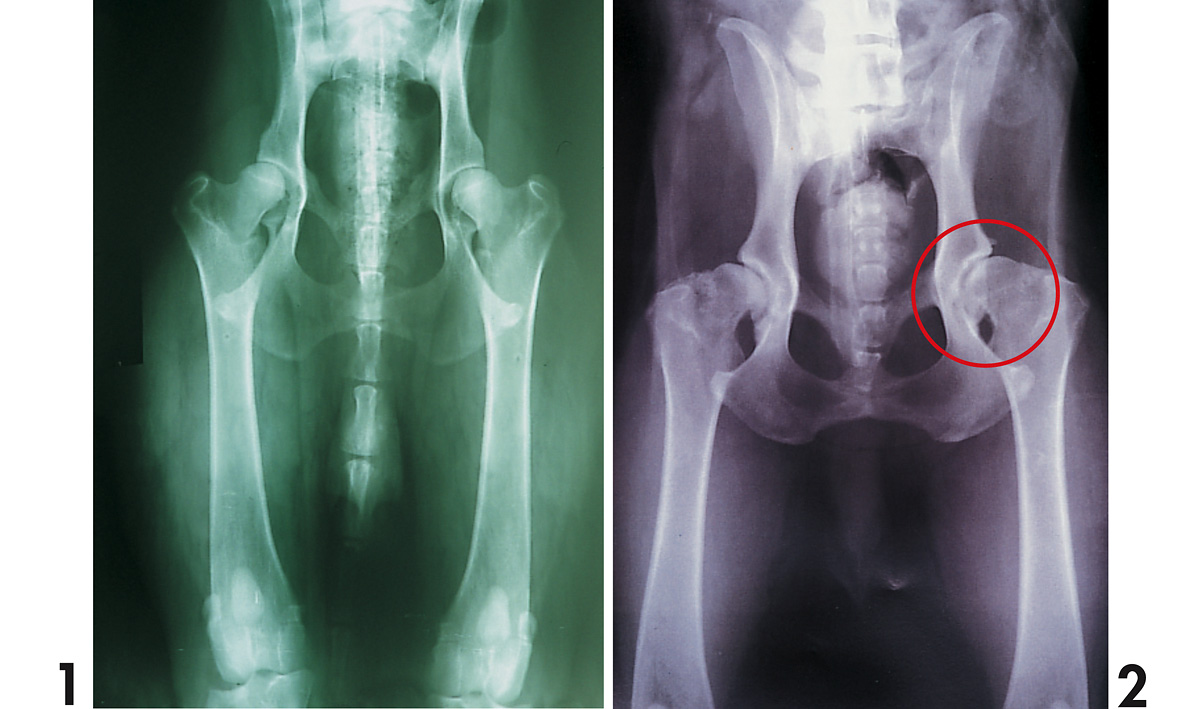

Antes de hacer efectiva la compra es fundamental pedir que nos muestren los pedigríes (documento de origen o árbol genealógico) del padre y de la madre. Allí figuran los nombres de los antepasados (hasta un máximo de cuatro generaciones) de nuestro futuro cachorro, los títulos y diplomas obtenidos, y la exención de displasia o el grado, en caso de aparecer esta patología hereditaria.